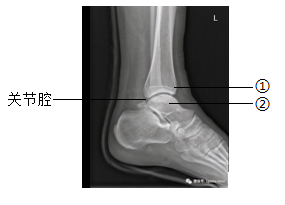

16. 下图为某人左脚的踝关节射线透视图像,①②表示踝关节内的结构。下列说法错误的是( )

A. ①是关节头,②是关节窝

B. ①②表面覆盖着关节软骨

C. 关节腔内有滑液,使关节灵活

D. 踝关节在运动中起枢纽(支点)作用

【16题答案】

【答案】A